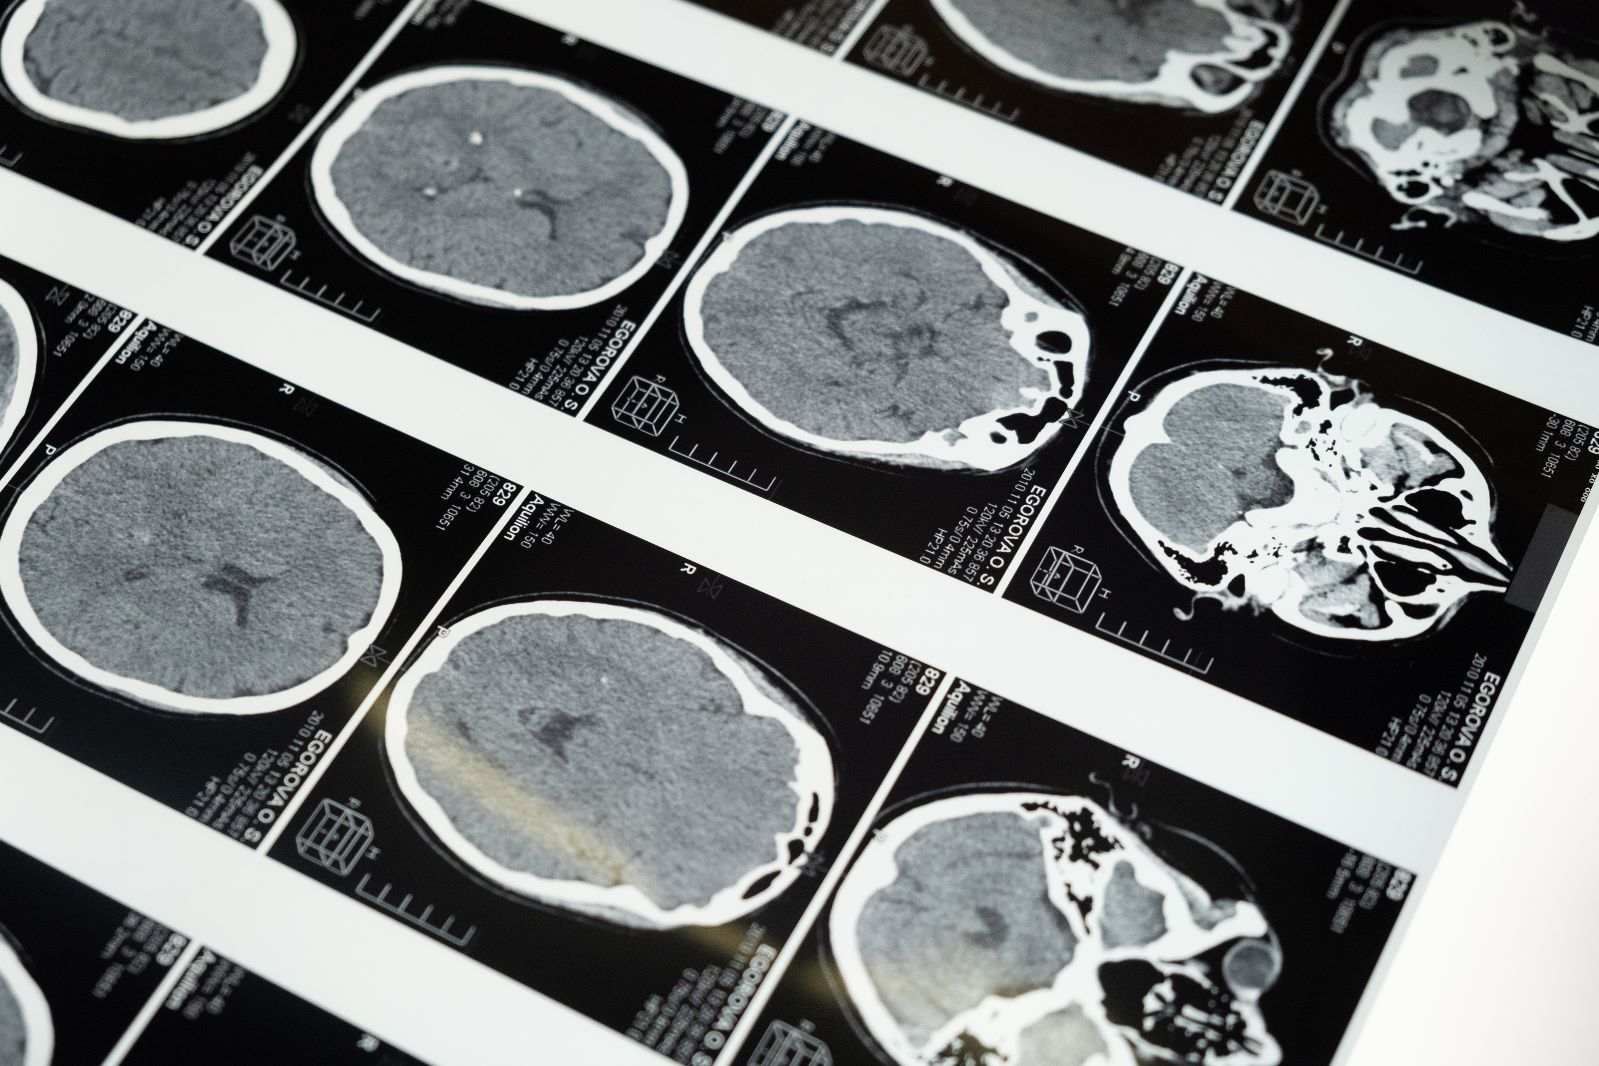

Bu olay beyin konusunda bilimin içinde bulunduğu acıklı durumu gösteriyor. Beyincik gibi bazı önemli bölgelerin işlevi konusunda bile fikir ayrılıkları var hala. Bu tür vakalar ortaya çıktığında beyin hakkındaki cehaletimiz de gün yüzüne çıkıyor. Hastanelerdeki beyin taramaları, beyin yapısının kişiden kişiye farklılık gösterebildiğini ortaya koyuyor. Bu farklılıkların, yakından gözlendiğinde davranışlarımız üzerinde etkili olduğunu görmek de mümkün olabilir.